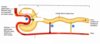

- externe (cortex rénal)

- intermédiaire (médullaire rénal ou médulla)

- interne (bassinet)

Que comprend la zone intermédiaire du rein et sa fonction?

- comprend tout les pyramide rénal (trait)

- chargé de retenir l’urine par la terminaire des pyramide (les papille rénal)

Que comprend la zone interne du rein et sa fonction?

interne (bassinet) retient l’urine avant de se déverser dans uretere, calice mineur sont à la terminaison des papile rénal et tous les calice mineur se réunisse pour former le calice majeur